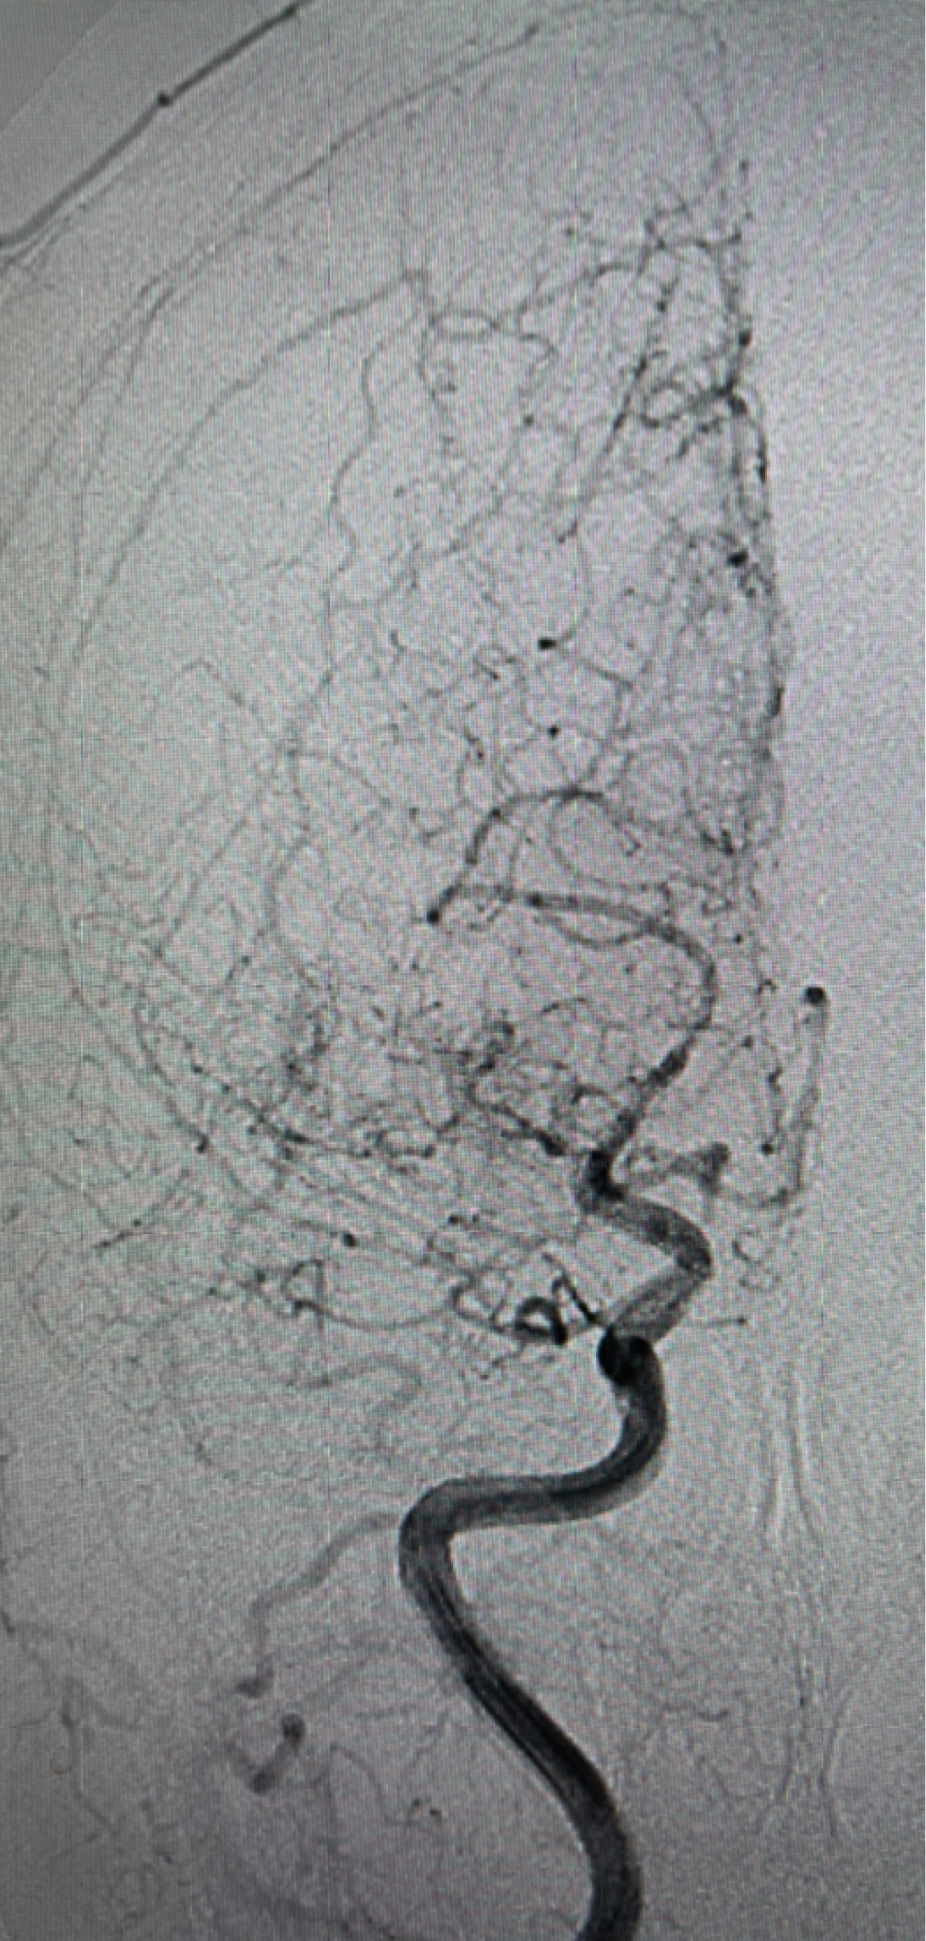

右侧颈内动脉造影提示大脑中动脉起始以远闭塞

颈内动脉侧位大脑前动脉A2以远闭全闭塞